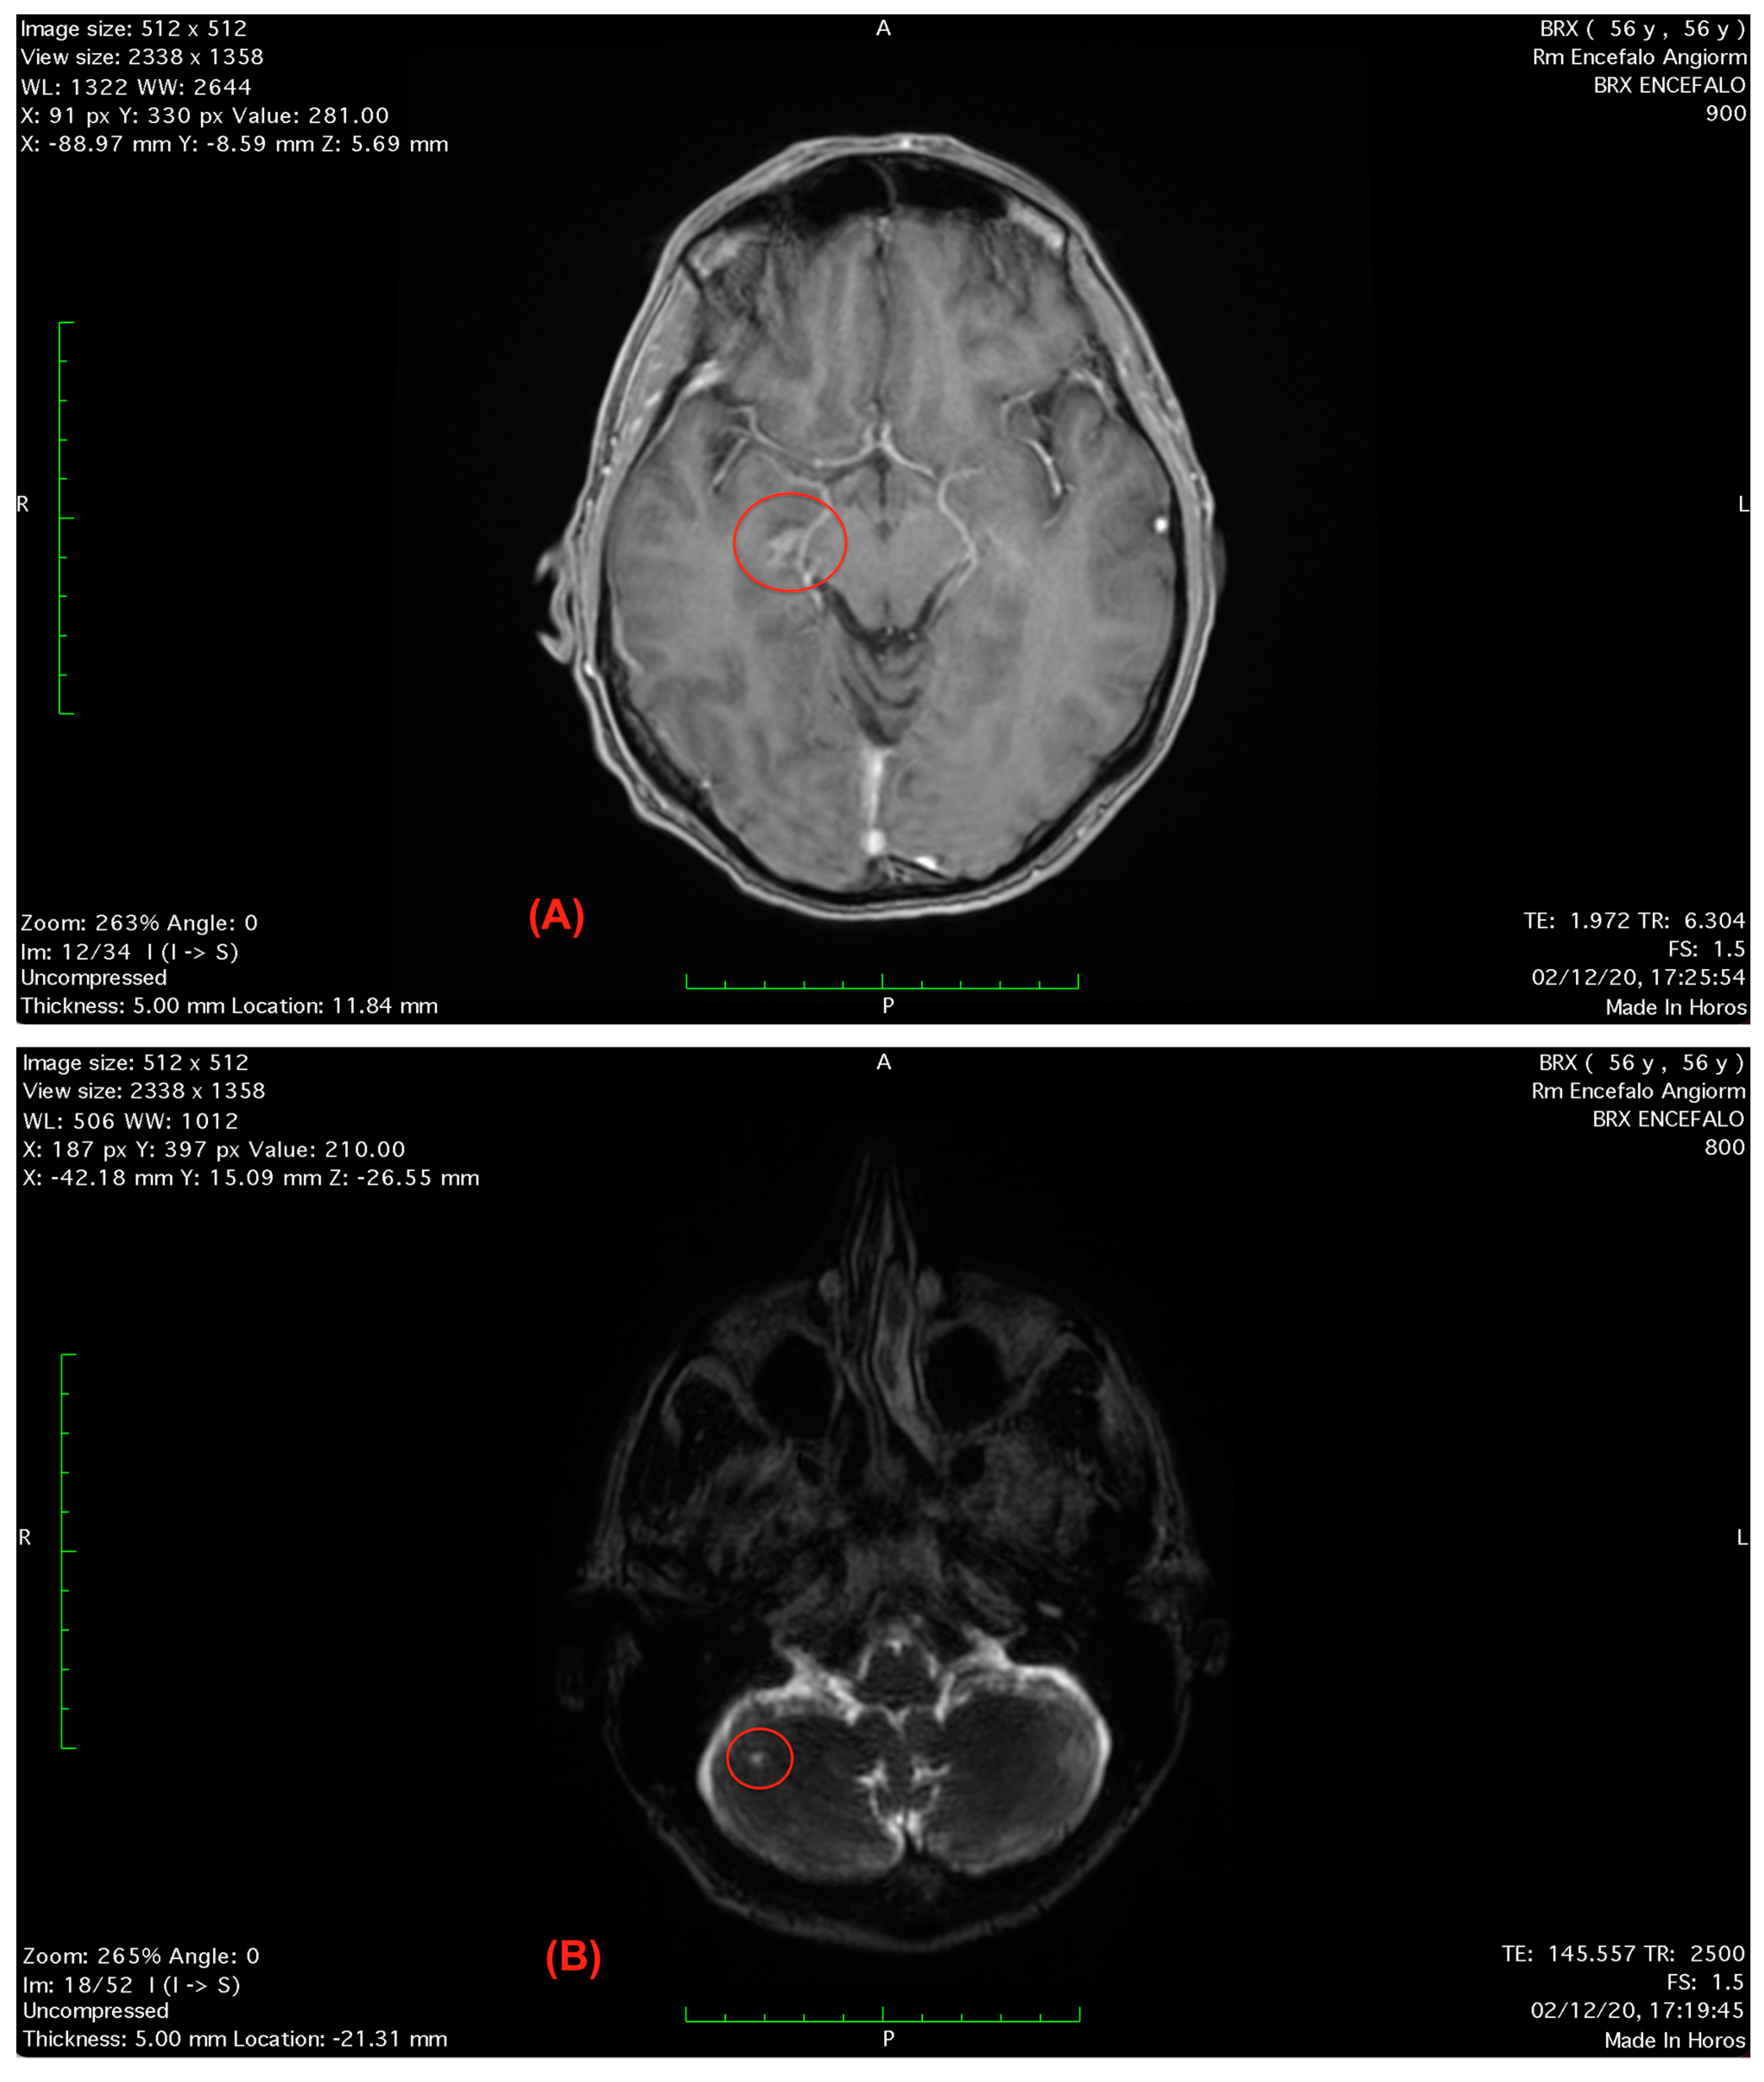

At the following heart surgeon visit, the electrocardiography and electroencephalogram testing were unremarkable; however, the routine blood testing revealed high levels of erythrocyte sedimentation rate 15 mm/h, creatine kinase 259 U/L, leukocytes 3.65 cells/μL and erythrocytes 12.8 cells/μL. Cranial computerized tomography scans were unremarkable, while brain magnetic resonance imaging scans showed two small hyper-intense areolas in correspondence to the lower right midbrain’s colliculus and to the ipsilateral cerebellar hemisphere [62] (Figure 2A,B).

Figure 2. (A) Axial T1-weighted FLAIR scan showing a small hyper-intense areola in correspondence to the lower right midbrain’s colliculus. (B) Axial T2-weighted brain magnetic resonance imaging scan showing the small hyper-intense areola in the right cerebellar hemisphere.